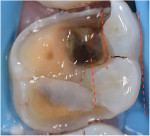

Regarding the assessment of clinical outcomes of restorative procedures, it is of paramount importance for clinicians to realize that the longevity of the tooth is a more accurate metric than the longevity of the restoration. Conservative preparations protect teeth from the trauma caused by the excessive use of rotary instrumentation (Figure 3 and Figure 4).

Regarding preparation design, the walls of preparations for partial-coverage restorations should be divergent to allow for path of insertion and have rounded angles to facilitate stress distribution. To develop a durable and long-lasting bond, the presence of enamel 360 degrees around the preparation's supragingival margin is essential (Figure 5). When assessing cuspal involvement, the preparation should include any cusp with a remaining thickness of less than 2 mm (Figure 7 and Figure 8). This is critical to maintain the integrity of the tooth and, subsequently, the restoration.